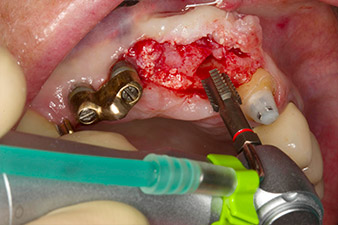

Xenogenic bone substitute material

Fig. 5: In order to achieve the best possible quality of peri-implant tissue, the site was additionally augmented with xenogenic bone replacement material and a collagen membrane in the scope of guided bone regeneration.